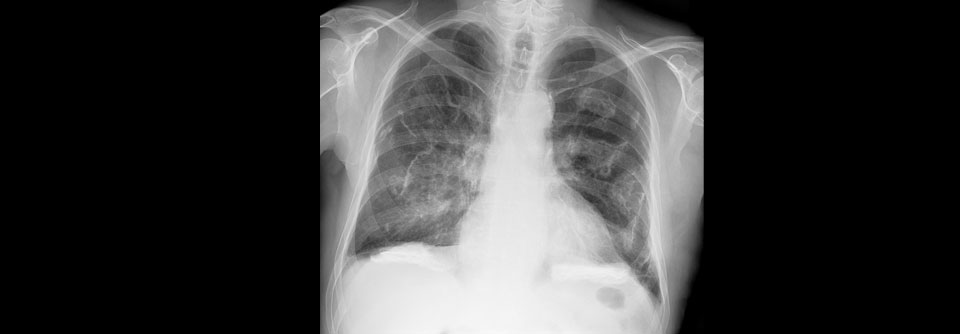

In jedem Fall gilt es, den Lungenumbau so gut wie möglich aufzuhalten. In jedem Fall gilt es, den Lungenumbau so gut wie möglich aufzuhalten. © iStock/magicmine

Häufig liegt Mosaikmuster vor

Histologisch finden sich bei der interstitiellen Lungenerkrankung im interstitiellen Gewebe…